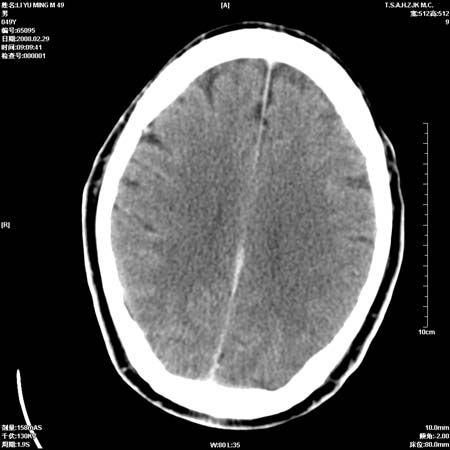

一周后复查ct:

可能为正常。间隔一周蛛血应基本吸收;再过一周复还是这样应该可以肯定了。

一周时间密度未见改变,考虑为正常图像(脑动脉硬化?)。